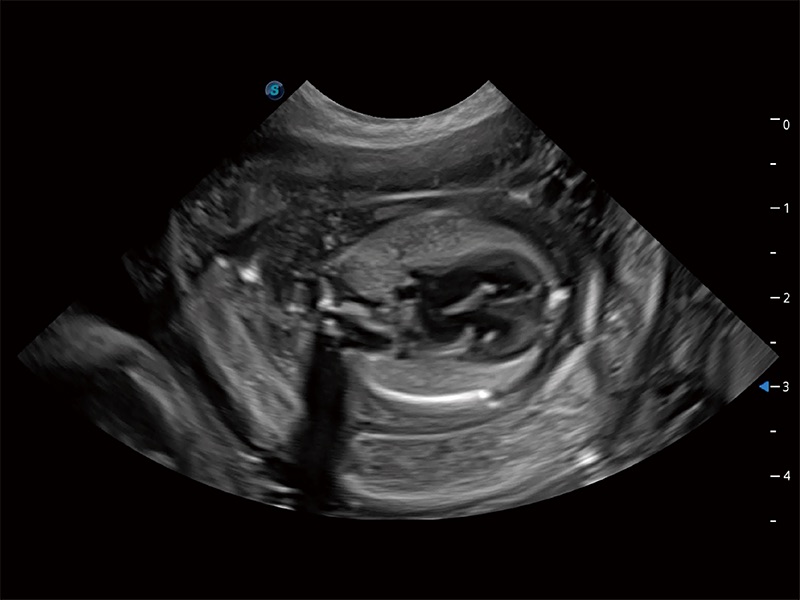

动物是人类最亲密的朋友和最值得信赖的伙伴。九州酷游也一直致力于探索动物专用的超声影像解决方案。全新推出的ProPet系列,是九州酷游在动物超声影像智能化、专业化、精准化的一次跨越式革新。动物不能用言语来表述自己的不适,通过超声影像,ProPet系列搭建了动物医生与不同物种沟通的“桥梁”,为动物医生注入了“治愈之力”。 ProPet 80 是九州酷游匠心打造的一款高端动物专用彩超,采用性能卓越的全新硬件架构,极大提升超声系统的运行效率和数据处理能力,帮助动物医生从容应对日益增多的挑战性病例和日益多样化的临床需求。

高性能和先进的临床应用工具可以为动物医生提供临床信心。ProPet 80 搭载了先进的腹部和浅表应用工具,帮助医生在日常临床实践中发挥前所未有的作用。

ProPet 80 专为动物医生设计,对不同的动物体型和生理结构作出了针对性的优化。通过动物影像专用软件,可满足个性化的应用需求,帮助动物医生获得更精确的诊断数据。